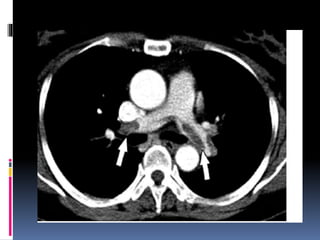

DISSECÇÃO DE AORTA

 FISIOPATOLOGIA:

 Ocorre em pacientes com alterações

degenerativas da camada média (perda de fibras

elásticas e musculares lisas da camada média,

que são substituídas por colágeno, com

predisposição a formação de cistos – necrose

cística)

 Havendo fissura do endotélio ou hematoma na

camada média → forma-se coluna de sangue na

parede do vaso (falso lúmem) separando a

camada íntima da adventícia → dor torácica e

predisposição a hemorragias fatais

 75% ♂; maioria na sétima década

 FR: Arterioesclerose, idade avançada, SD de Marfan, Sd de

Turner, HAS

 CLÍNICA:

 Dor de início súbito, de forte intensidade (máxima no

momento do aparecimento) – com esse quadro, 90% de

sensibilidade na detecção; persistente

 Dor descrita como “rasgando”, em região anterior e

posterior do tórax, podendo irradiar para costas, região

interescapular e abdome

 Pode estar associado com a manifestação de AVC, síncope,

Insuf. Cardíaca, IAM, isquemia isolada em membros, dor

abdominal, IRA ou sangramentoGI. (dependendo da altura

da lesão)

 E. F.:

 Comum achado de assimetria de pulsos ou

sintomas neurológicos

 Sinais de má perfusão tecidual

 Ex. cardiológico:

- pode revelar sopro diastólico de aorta

(qdo dissecção progride até valva aórtica)

- pode ter estase jugular secundária a

tamponamento cardíaco.